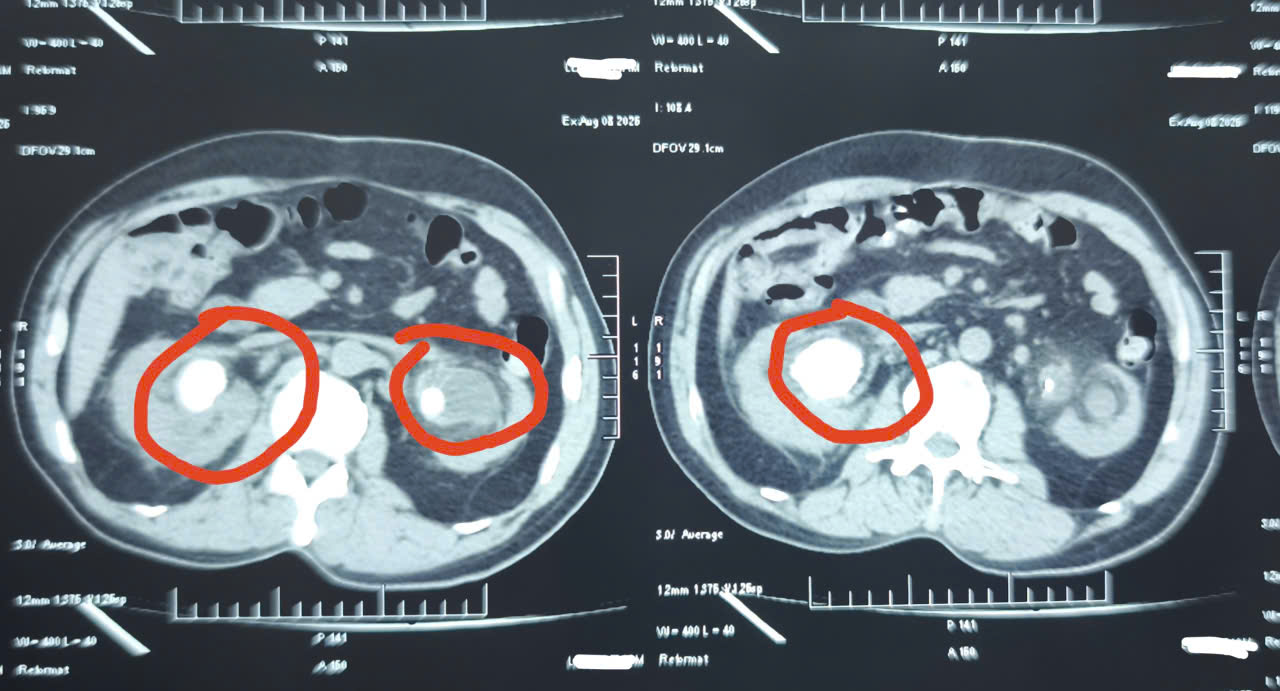

Tổn thương thận có thể gây nước tiểu sủi bọt, sưng chân hoặc mặt, tiểu đêm thường xuyên, nước tiểu sẫm màu, mệt mỏi mãn tính, và vị kim loại hay amoniac trong miệng. Thận...